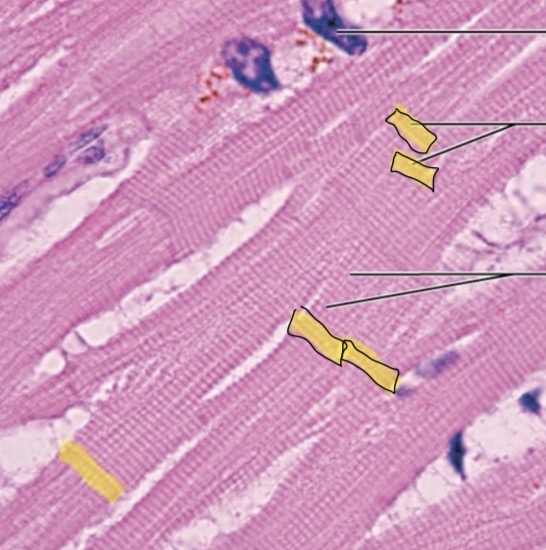

Heart

Intercalated Discs